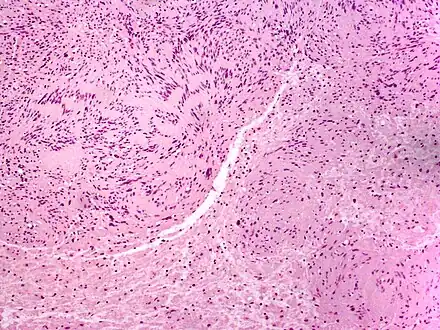

| Micrograph of a palisaded encapsulated neuroma | |

Palisaded and Encapsulated Neuroma